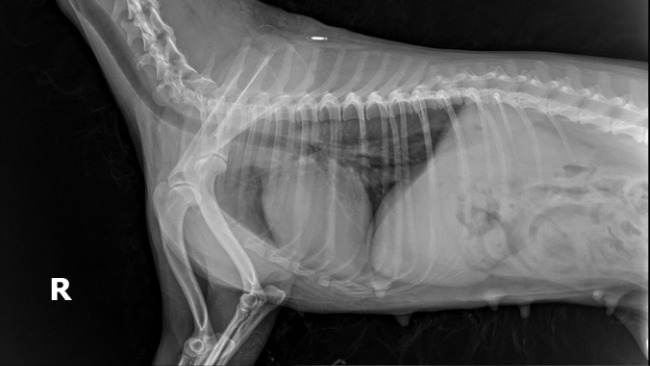

Jest niewykastrowana, z guzem na listwie mlecznej.

Musimy wykonać u niej badania krwi, badanie RTG klatki piersiowej i jeśli wszystko będzie dobrze, konieczny jest zabieg kastracji wraz z mastektomią, czyli usunięciem części listwy mlecznej.